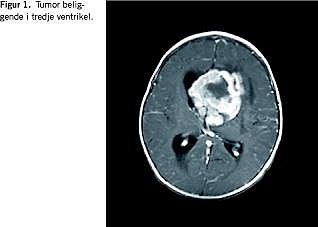

En seks måneder gammel pige blev akut indlagt pga. idelige opkastninger, der efterhånden var af eksplosiv karakter. Hun havde skrantet i en uge, spist sparsomt, gylpet mere end vanligt og været subfebril. Ved indlæggelsen var hun afebril, men slap og sløv. Efter et halvt døgns indlæggelse fik hun et tonisk krampeanfald. Kramperne blev brudt med sup. stesolid klysma. Der fandtes nu pupildifferens med dilateret venstre pupil, der reagerede trægt for lys. Akut computertomografi af cerebrum viste en stor tumor i tredje ventrikel. Lateralventriklerne var voldsomt dilaterede. I begge hemisfærer sås ødem og begyndende inkarceration.

Patienten blev overflyttet til Neurokirurgisk Afdeling, Århus Sygehus. Her blev der akut anlagt ventrikeldræn bilateralt. Magnetisk resonans (MR)-skanning (Figur 1 ) viste en stor malignt udseende tumor intraventrikulært. Ved operation blev tumor fjernet subradikalt, fordi den var placeret op ad de centrale vener basalt. Frysemikroskopi under operationen viste anaplastisk ependymom, men ved efterfølgende patologisk undersøgelse blev diagnosen korrigeret til AT/RT.